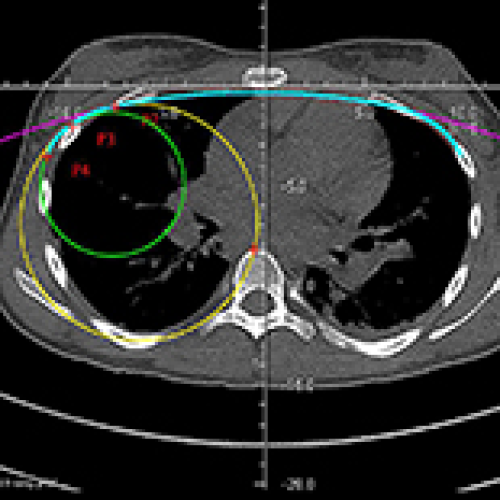

18 May 2024 : Clinical Research

New Computerized Planning Algorithm and Clinical Testing of Optimized Nuss Bar Design for Patients with Pectus Excavatum

János György Papp, Ákos Kiss

DOI: 10.12659/MSM.943705

Med Sci Monit 2024; 30:e943705

János György Papp, Ákos Kiss, Krisztián Balogh, László Kostyál, Imre Tóth, Tibor Gáll, Péter Vajda

, Tamás F. Molnár, István Papp, László Szabó, Árpád B. Palotás

4,456